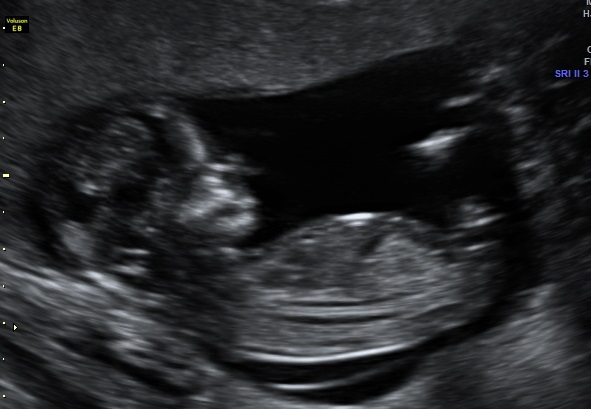

I'm new to posting on these sites, however my curiosity has the better of me so I've taken out my 13 week scan images and was hoping someone could provide me any thoughts as to whether I'm having a boy or a girl. I've read the theory on the "nub" but still cannot make out the gender with my limited knowledge.

The pictures posted below were the four best I had from the 13 week scan.

Girl. Long straight and parallel to spine:)